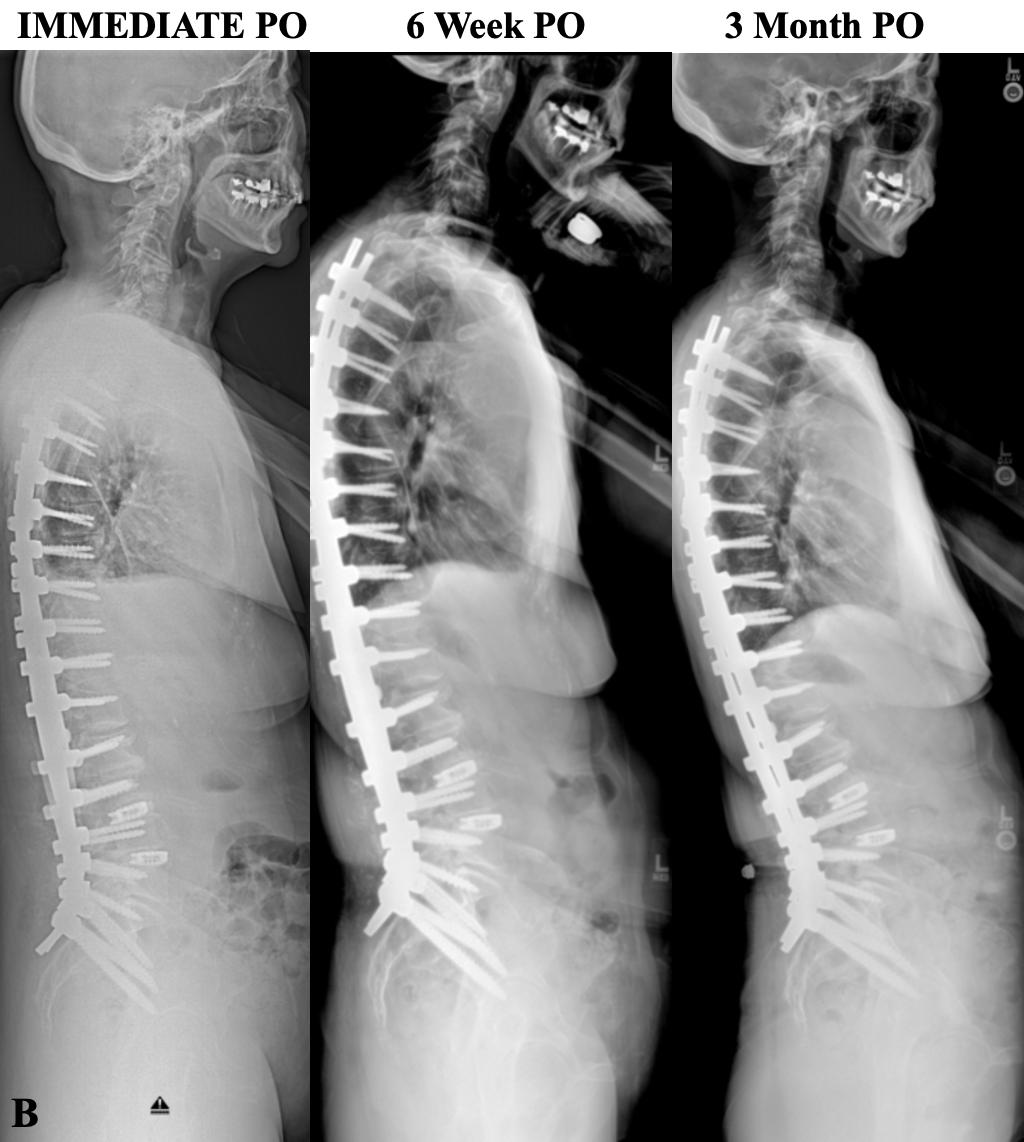

Figure 1. Preoperative and postoperative (PO) radiographic evaluation of adult spinal deformity with T4-L1-hip axis planning. (A) Standing anteroposterior and lateral scoliosis radiographs demonstrating preoperative and postoperative coronal alignment. The preoperative image reveals adult idiopathic scoliosis (Lenke 6) with a lumbar curve of 75° and main thoracic curve of 50°. The postoperative anteroposterior radiograph demonstrates correction following posterior spinal instrumented fusion from T4 to pelvis. (B) Lateral scoliosis radiographs of preoperative, planning, and postoperative radiographs with corresponding T4-L1-hip axis parameters. The patient’s pelvic incidence (PI) of 40° establishes a target L1-pelvic angle (L1PA) of −1° based on the equation L1PA = PI × 0.5 − 21°. Preoperatively, the patient demonstrated L1PA of 2°, T4PA of 19°, and C2PA of 24°, indicating marked thoracolumbar kyphosis. The surgical plan targeted restoration of L1PA to −3°, T4PA to 3°, and C2PA to 7°, maintaining T4-L1PA mismatch within the optimal range of −3° to +1°. Postoperative radiographs confirm achievement of planned alignment with L1PA of −3°, T4PA of 3.5°, and C2PA of 10.5°. The T4-L1PA mismatch of +17° was preoperatively reduced to +6.5° postoperatively.